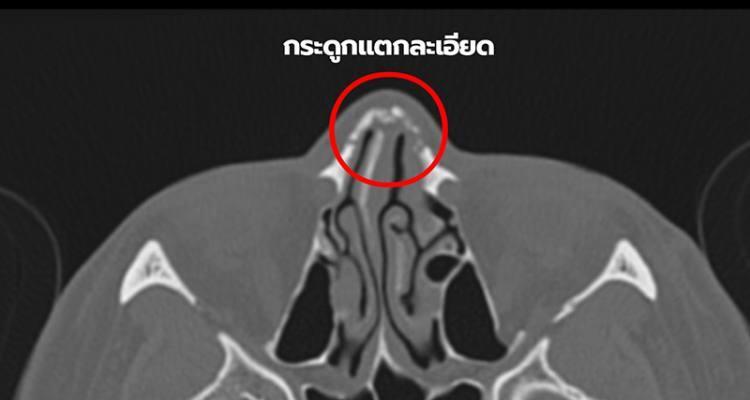

หลังจากที่เคยกลายเป็นข่าวใหญ่สุดหดหู่ กรณี “น้องเอ” อดีตทหารหญิงรับใช้ ถูกนายจ้าง ส.ต.ท.หญิง ทำร้ายร่างกาย ทั้งเตะ ต่อย ช็อตไฟฟ้า เอารองเท้าตบปากแล้วเอาน้ำยาล้างห้องน้ำราดซ้ำ เอาฟุตเหล็กฟันใส่หน้าหลายครั้ง ทำให้จมูกแตกละเอียด หายใจได้ข้างเดียว ตามีร่องรอยถูกทำร้าย ส่งผลถึงการมองเห็น หน้าผาก คาง ใบหน้าผิดรูป ใบหน้าได้รับความเสียหายร้ายแรง โพรงจมูก คดงอ กระดูกแตกละเอียด

โดยทีมศัลยแพทย์ตกแต่งแจ้งว่า จากการตรวจร่างกาย ร่วมกับการทำเอ็กซเรย์คอมพิวเตอร์บริเวณใบหน้า พบว่า กระดูกจมูกฝั่งซ้ายแตกละเอียดและผนังกั้นจมูก คดงอ มาทางด้านซ้ายอย่างมาก เป็นผลให้การหายใจติดขัด สามารถหายใจได้ด้วยโพรงจมูกด้านขวาเพียงด้านเดียวเท่านั้น ในส่วนของกระดูกจมูกฝั่งซ้ายที่แตกละเอียด ได้ทำการจัดเรียงกระดูกที่แตกละเอียดด้วยเทคนิคพิเศษเพื่อให้การสมานของกระดูกได้สัดส่วนกับรูปหน้า ในส่วนของผนังจมูกที่คดไปด้านซ้าย ได้ทำการผ่าตัดแก้ไขกระดูกอ่อนของผนังจมูกและปรับทางเดินหายใจด้านซ้ายที่อุดตัน ทำให้กลับมาหายใจด้วยโพรงจมูกด้านซ้ายได้เป็นปกติ